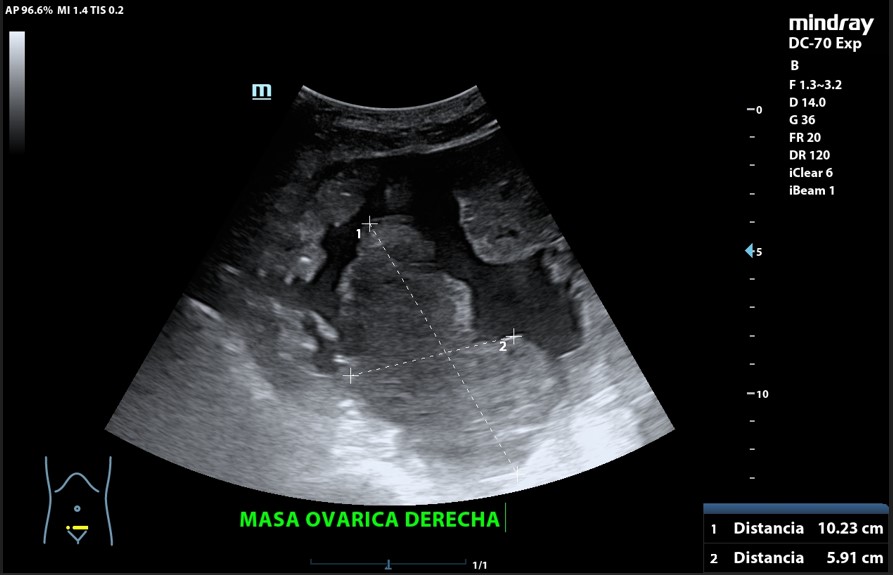

Presencia de 2 masas pélvicas bien delimitadas heterogéneas que captan Doppler, una de 5 cm de diámetro y otra ovalada de 10 cm de longitud. Líquido ascítico peritoneal, que también se observa alrededor del bazo y en espacio de Morrison. Derrame pleural derecho.

Tumoración ovárica bilateral.